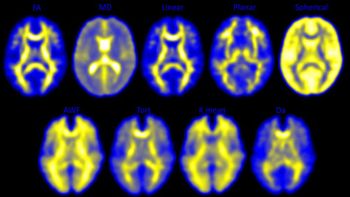

Imaging exams detect structural and functional changes in the brains of high school football players, from RSNA 2016.